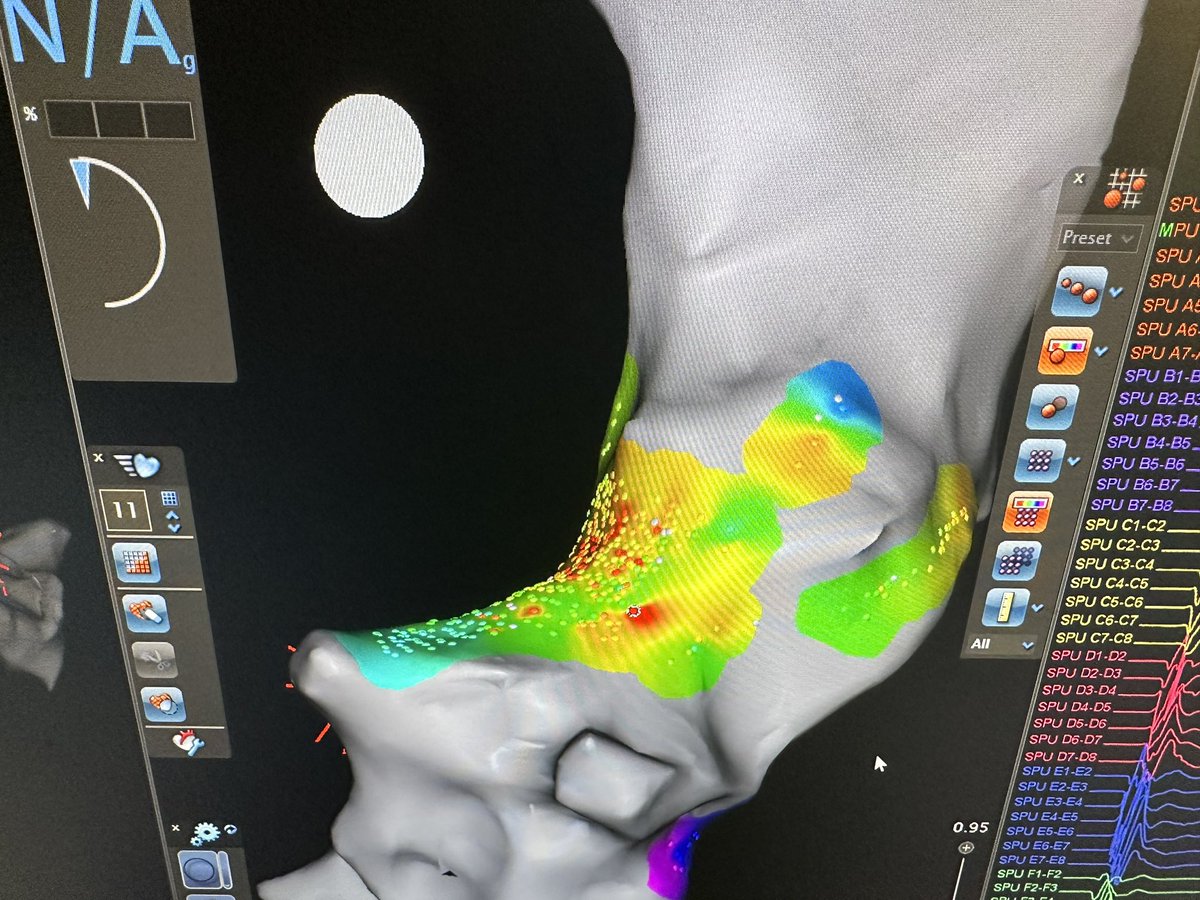

Difficult mitral isthmus line after mitral flutter induced post atrial fibrillation ablation. Intermittent block with multiple endocardial burns. Bidirectional block after VOM injection with dramatic increase in endocardial scar on right @VirtuaHealth @VirtuaHRS @AatishGarg_EP

@AatishGarg_EP @VirtuaHealth @VirtuaHRS @jaykoneru @KennethEllenbo1 @MiguelVldrbno @EPbordeaux @HeathHsalt Great work on first case. 3 minutes of endocardial burns to get bidirectional mitral isthmus block is no joke